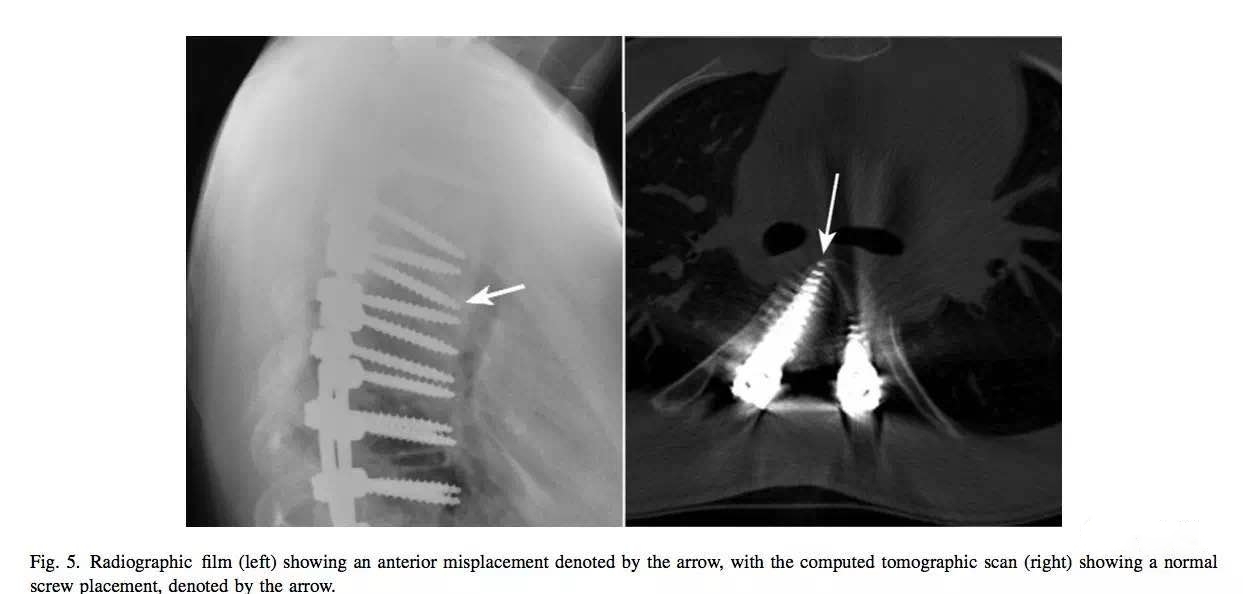

X线片显示钉子太长,但CT复查显示钉子在椎体内。